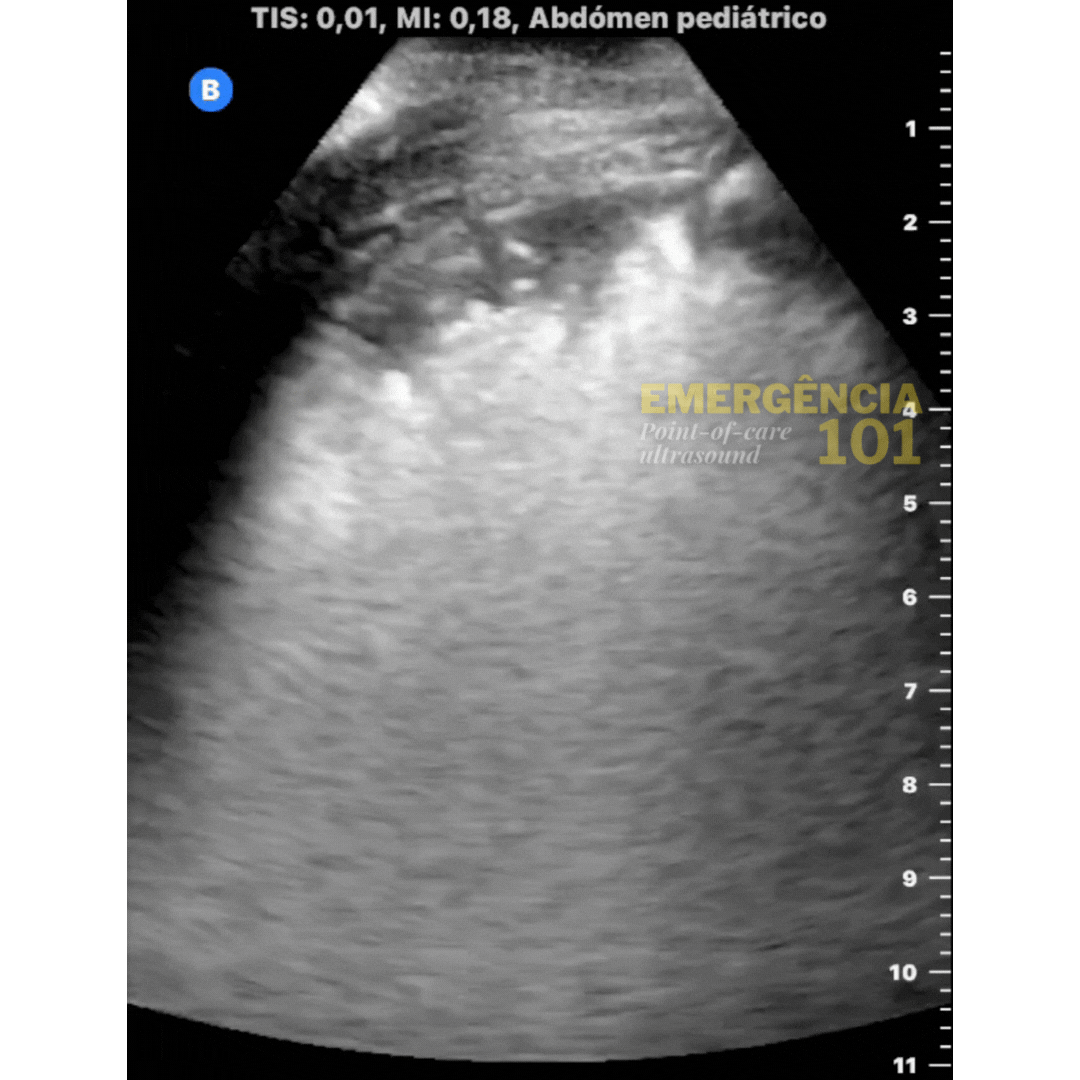

Figura 6a. Hepatização pulmonar em paciente pediátrico, com presença de broncogramas aéreos dinâmicos —representados por essa imagem hiperecóica (branca) dentro do parênquima pulmonar — que se movem com a respiração do paciente. Acervo pessoal do autor.

Figura 6b. Hepatização pulmonar em paciente pediátrico, com presença de broncogramas aéreos estáticos — sem movimento — dentro do parênquima pulmonar. Acervo pessoal do autor.